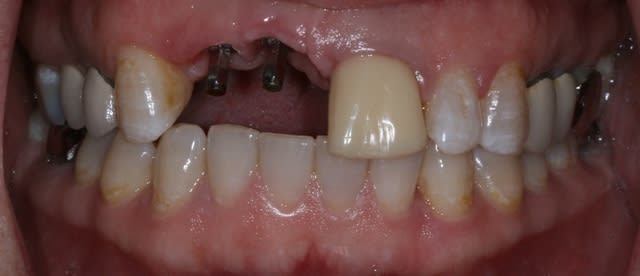

Patiente de 30 ans suite à parodontite a perdu 11-12 avec grosse perte osseuse.

J'ai suffisamment d'os pour prévoir la pose implantaire sans greffe mais esthétiquement je pense que cela va être moche car la ligne du sourire me semble bien haute.

si tu implantes comme ça, on est bien d'accord que ça va être moche.

que comptes tu faire de la 21? as tu une rétro?

Bon ben j'ai implanté avant d'avoir refait la 21. Du coup j'ai mésialé la pose de 11 pour compenser la distalisation de 21.

Au final je n'ai pas fait de greffe osseuse... et j'ai réalisé une technique de rouleau sur 11-12 mais je reste un peu court à mon goût.

J'ai mis en place des transitoires sur 11-12-21 pour temporiser 3 mois pour voir la maturation des tissus mous.